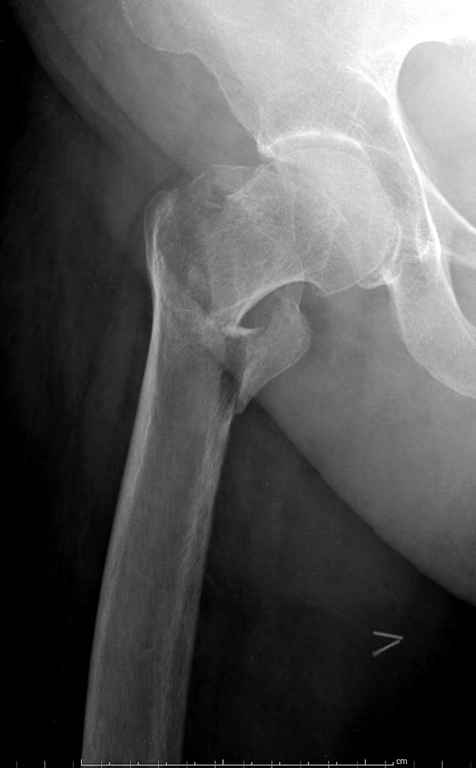

Перелом тут больше подвертельный. Нагрузка без торцевого упора на уровне перелома привела к телескопированию отломков на стержне. Ну и варус небольшой тоже свою лепту внес - если бы его не было, контактирующие латеральные стенки обоих отломков предотвратили бы укорочение, да и срослось бы за пару месяцев. А раз не срослось, упора отломков нет, более слабым местом оказались не нижние винты, а кость в головке и шейке. Так что надо было хотя бы удалить нижние винты до начала полной нагрузки.

Фиксация * reversed obliquity* подвертельных переломов - дело непростое.

На мой взгляд, причиной телескопирования явилось несоответствие диаметра гамма нэйл с диаметром канала подвертельного отдела бедра: обратите внимание на величину протрузии шеечного винта и величину медиализации дистального фрагмента - они одинаковы, смещение или телескопирование фрагментов происходило до того момента, пока гамма нэйл не упёрся в медиальный кортекс и образовалось пространство между латеральным

кортексом и латеральной поверхностью гвоздя.

E> На мой взгляд, причиной телескопирования явилось несоответствие

E> диаметра гамма нэйл с диаметром канала подвертельного отдела бедра:

Диаметр гаммы в диафизарной части ~11 мм. А диаметр канала, тем более у пожилых с остеопорозом, может быть мм 15. Даже рассверливать обычно не приходится, после формирования широкого канала в вертельной области можно сразу толкать гвоздь, он влетает, как карандаш в стакан. Так что соответствия диаметров не бывает никогда. Однако представленная ситуация случается далеко не каждый раз. Если гвоздь в центральном отломке входит чуть медиальнее верхушки вертела, и идет вдоль передне-латеральной стенки центрального отломка, то все будет хорошо.

Здраствуйте. По данному снимку видно 2-а основных момента которые привели к протрузии винта в вертлужную впадину: 1) шеечный винт дистальной поверхностью наружнего края "зацепился" за латеральный кортикал бедра, это не дало сработать динамической системе гвоздь-винт. 2) лучьше шеечный винт проводить ближе к дуге Адамса, там болееплотная костная ткань. Решенее: как подготовка к эндопротезированию, реостеосинтез, можно такой же системой, но с учетом упомянутых моментов, максимальное безнагрузочное ЛФК (без боли).